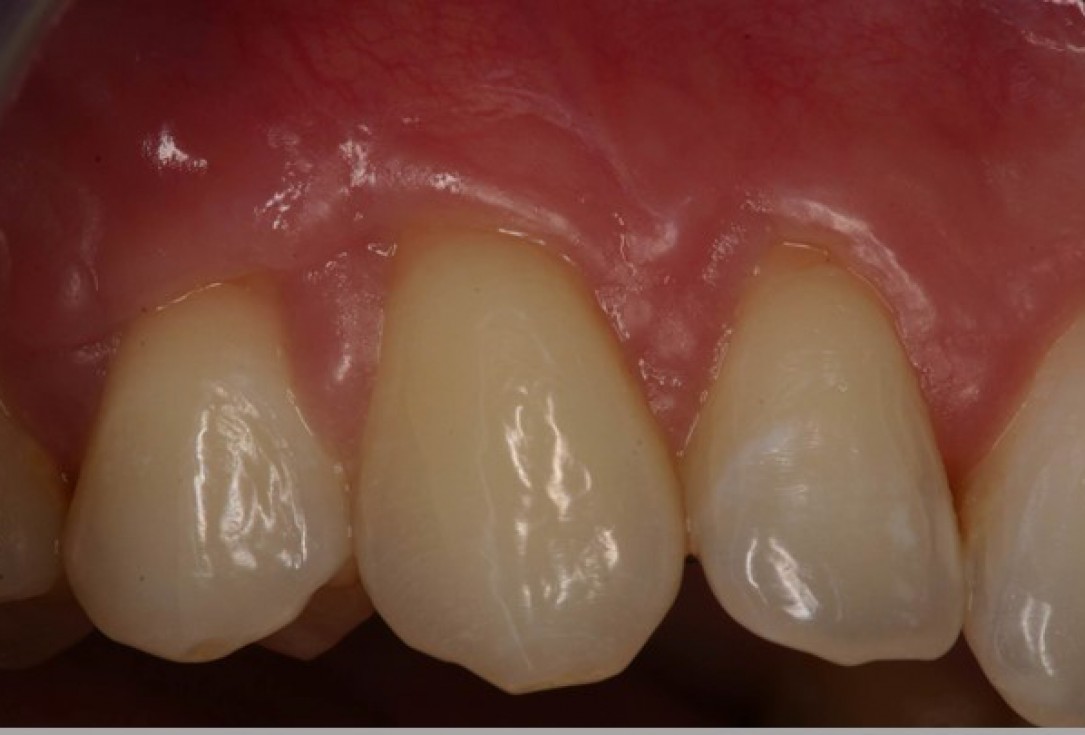

05/06 - Clinical situation 3 months post-operative. Significant coverage of the roots and increased thickness of the marginal tissue.Multiple gingival recessions treated with the modified coronally advanced flap in conjunction with mucoderm® - Prof. Dr. Dr. A. Kasaj

06/06 - Clinical situation 18 months post-operative.Multiple gingival recessions treated with the modified coronally advanced flap in conjunction with mucoderm® - Prof. Dr. Dr. A. Kasaj